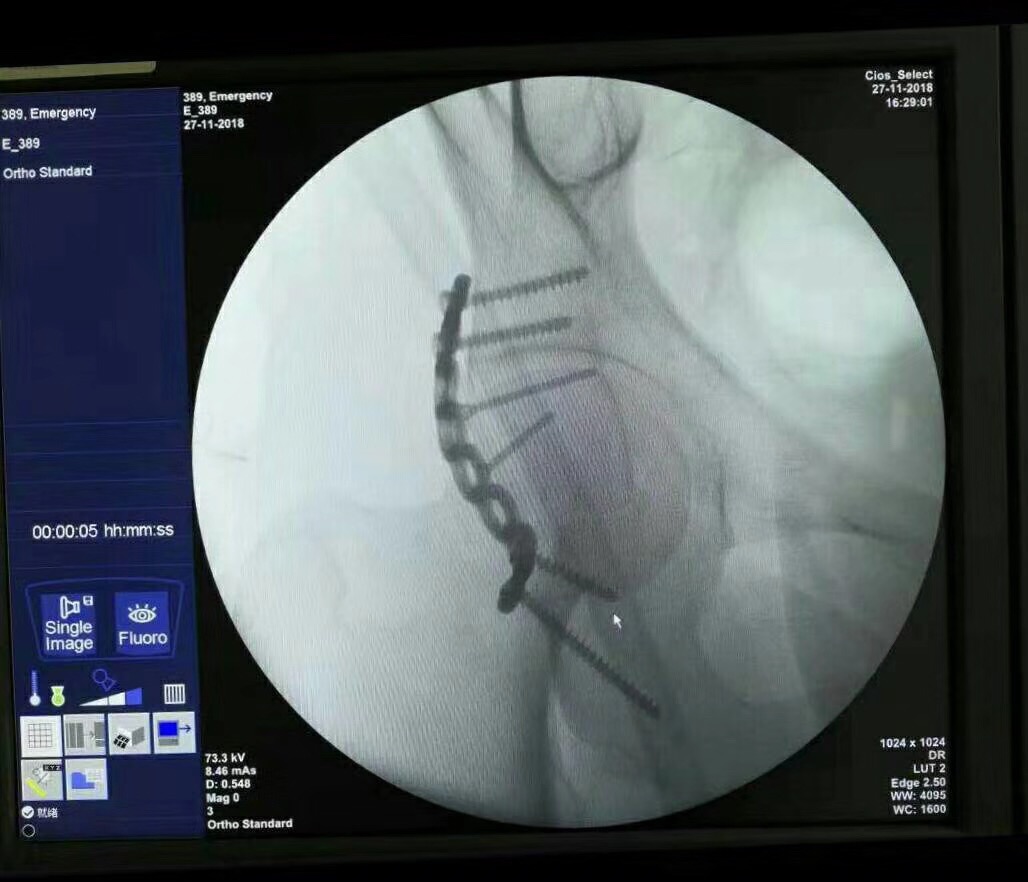

術(shù)中直接植入鋼板

通過(guò)線片觀察鋼板植入情況